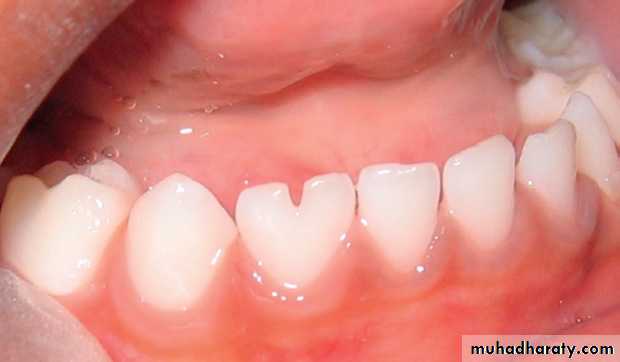

1. Talon cusp